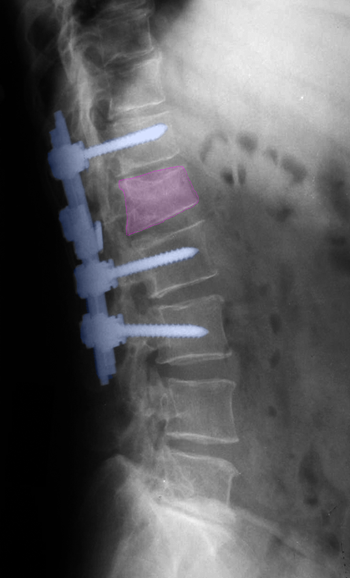

Περιγραφή Η οσφυϊκή σπονδυλοδεσία πραγματοποιείται με γενική αναισθησία, με τον ασθενή σε πρηνή θέση και υπό ακτινοσκοπικό έλεγχο. Η τομή δέρματος γίνεται στο μέσο της ράχης, επί των σπονδύλων που πρόκειται να συνδεθούν. Τα οπίσθια στοιχεία τους παρασκευάζονται και κατόπιν τοποθετούνται βίδες από κράμα τιτανίου στα σώματα των σπονδύλων (2 σε κάθε ένα). Οι κεφαλές των βιδών συνδέονται με ράβδους και έτσι επιτυγχάνεται συνένωση των σπονδύλων σε μία κινητική μονάδα αφού προηγουμένως έχει γίνει ανάταξη της διαταραχής της ανατομίας, (αν αυτή προϋπάρχει όπως στη σπονδυλολίσθηση ή τα κατάγματα) με τη βοήθεια ειδικών εργαλείων. Η σπονδυλοδεσία συμπληρώνεται με τοποθέτηση οστικού μοσχεύματος γύρω από το σύστημα σπονδυλοδεσίας προκειμένου να επιτευχθεί αργότερα (σε ορίζοντα μηνών) σταθεροποίηση της σπονδυλικής στήλης μέσω οστεοσύνθεσης, δηλαδή δημιουργίας νέου οστού το οποίο συνενώνει τους σπονδύλους. Αυτό είναι και ο τελικός σκοπός της επέμβασης. Η ανωτέρω περιγραφόμενη μέθοδος ονομάζεται οπίσθια σπονδυλοδεσία με διαυχενικές βίδες και ράβδους και γίνεται συχνά σε συνδυασμό με οσφυϊκή πεταλεκτομή για να αποσυμπιεστούν τα νευρικά στοιχεία που πιέζονται από την εκφυλιστική νόσο, το κάταγμα ή τον όγκο της σπονδυλικής στήλης. Μια άλλη μέθοδος σπονδυλοδεσίας, με την ίδια οπίσθια προσπέλαση, είναι η τοποθέτηση μεσοσπονδυλίων εμφυτευμάτων τύπου PLIF, η οποία όμως απαιτεί πάντα οσφυϊκή δισκεκτομή γιατί η τοποθέτηση τους γίνεται στη θέση του αφαιρεθέντος μεσοσπονδύλιου δίσκου. Τα εμφυτεύματα αποτελούνται από τιτάνιο ή ειδικό πολυμερές πλαστικό και χρήζουν και αυτά συνοδεία οστικού μοσχεύματος για να επιτευχθεί οστεοσύνθεση. Η δυνατότητα ανάταξης ανατομικής διαταραχής και σταθεροποίησης είναι όχι μεγάλη με τη βοήθεια αυτής της μεθόδου και γι' αυτό συνδυάζεται συχνά με οπίσθια διαυχενική σπονδυλοδεσία. Η πρόσθια οσφυϊκή σπονδυλοδεσία, με προσπέλαση μέσω της κοιλιακής χώρας, χρησιμοποιείται σπανιότερα, και κατά κανόνα σε ασθενείς με βαριά ανατομική προβληματική συμπεριλαμβάνουσα και τα σπονδυλικά σώματα. Αντενδείξεις και επιπλοκές Οι αντενδείξεις της οσφυϊκής σπονδυλοδεσίας δεν είναι πολλές. Οι σημαντικότερες είναι η κακή ποιότητα οστού, όπως στην προχωρημένη οστεοπόρωση, η οποία καθιστά την ενσφήνωση των βιδών στο σπονδυλικό σώμα επισφαλή και κατ' επέκταση το σύστημα σπονδυλοδεσίας επιρρεπές σε αστοχίες, και η ενεργός λοίμωξη. Οι επιπλοκές της οσφυϊκής σπονδυλοδεσίας είναι συχνότερα παθολογικού χαρακτήρα όπως η πνευμονική λοίμωξη και η θρόμβωση των κάτω άκρων και σπανιότερα χειρουργικές όπως η αποτυχία συνοστέωσης και ο τραυματισμός της μήνιγγας ή/και των οσφυϊκών νεύρων. |